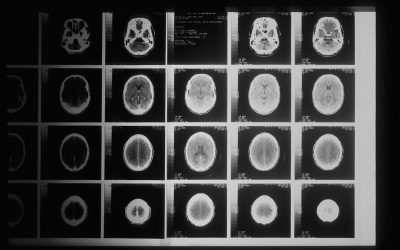

Was in Deinem Gehirn passiert, wenn Überforderung zurückkommt

Um zu verstehen, warum Du wieder so schnell überfordert bist, lohnt sich ein Blick in Dein Gehirn. Nicht theoretisch, sondern ganz praktisch. Dein Gehirn arbeitet stark mit Automatismen, die über Jahre eingeübt wurden. Es bewertet ständig, ordnet alles in „gut“ oder „schlecht“ ein und reagiert oft schneller, als Dein bewusster Verstand folgen kann. Und genau hier entsteht Überforderung:

Dein Stammhirn kennt keinen Unterschied zwischen „real“ und „gedacht“.

Wenn ein Gedanke nach Stress, Kritik oder Bedrohung klingt, schaltet Dein System auf Alarm – selbst dann, wenn objektiv nichts Dramatisches passiert. Dabei greifen häufig mehrere automatische Denkfallen gleichzeitig: